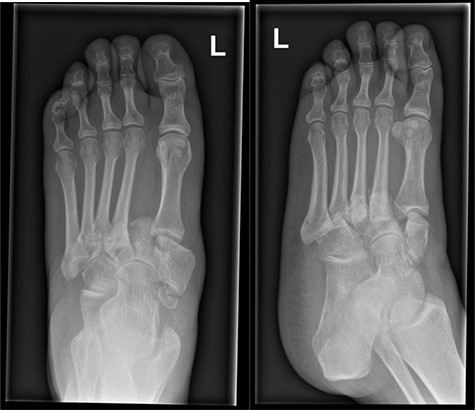

Post-operative X-rays (AP and lateral), demonstrating good reduction and fixation of fracture dislocations.

The patient was initially managed with a total contact leg cast, followed by open reduction and internal fixation (ORIF) with locking plates, combined with lengthening of the tendo-Achilles to permit full dorsiflexion and subsequent re-casting (Fig. 5). Her post-operative progress was satisfactory, and she is currently non-weight bearing for 6 months post-ORIF.